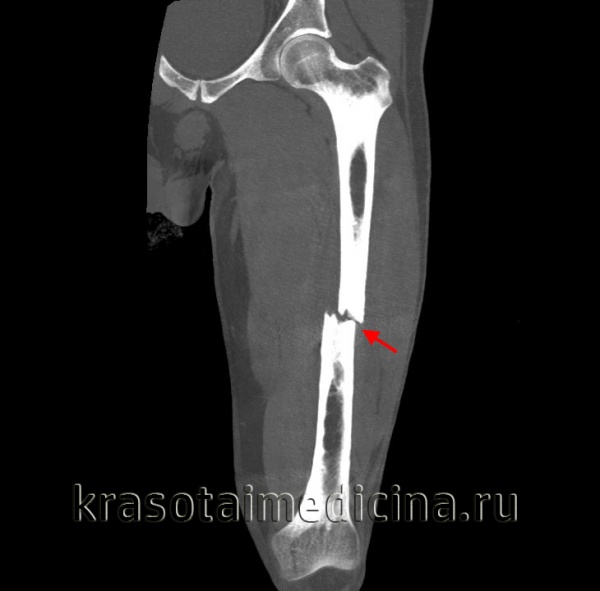

Для уточнения диагноза выполняют обзорную рентгенографию таза и рентгенографию поврежденного сустава в трех дополнительных проекциях. По возможности пациента направляют на КТ таза, поскольку эта методика позволяет более точно оценить тяжесть травмы и характер смещения отломков. Диагностическая ценность компьютерной томографии возрастает при повреждениях задней колонны и оскольчатых переломах.

Переломы вертлужной впадины могут оказаться трудными для выявления на первичных рентгенограммах таза в прямой проекции. При подозрении на эти повреждения важно тщательно изучить нормальные анатомические ориентиры, окружающие вертлужную впадину и изображенные на рис. 176. При подозрении на перелом вертлужной впадины следует сделать рентгеновские снимки в следующих проекциях:

Задняя опора и передняя губа лучше просматриваются на снимке в наружной косой проекции под углом 45°, в то время как задняя губа и передняя опора — на снимке во внутренней косой проекции под углом 45°. Кроме того, переломы заднего столба будут искажать подвздошно-седалищную линию, в то время как переломы передней опоры приведут к деформации подвздошно-лонной линии. Центральные переломы вертлужной впадины лучше выявляются на задней косой проекции. Некоторые виды переломов таза нередко сочетаются с переломами вертлужной впадины, которые не всегда легко выявить рентгенологически.

Прямая проекция тазобедренного сустава (вертлужной впадины). У больного с подозрением на перелом следует тщательно осмотреть эти линии. При скрытом переломе может наблюдаться смещение только одной из этих линий